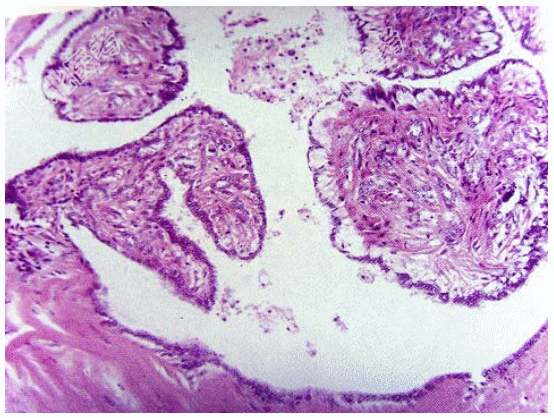

- [材料题] 女性,35岁,左侧乳头血性溢液半月余,乳头附近扪及柔软、樱桃大小包块,尚可活动。超声显示肿块界限清楚,低回声结节。手术切除,显微镜下管腔内见树枝状结构,乳头和导管共存(如图)。临床诊断为导管内乳头状瘤。